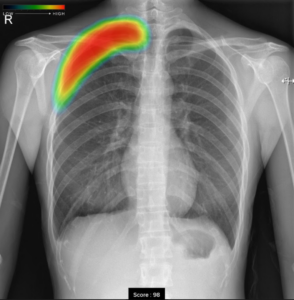

本特徴としましては、AI技術を活用して胸部単純X線画像から結節・腫瘤影、浸潤影、気胸の3つの画像所見を検出し医師の画像診断を支援するものです。

撮影した胸部単純X線画像を自動解析し、結節・腫瘤影、浸潤影、気胸が疑われる領域を検出しマーキングします。

気胸